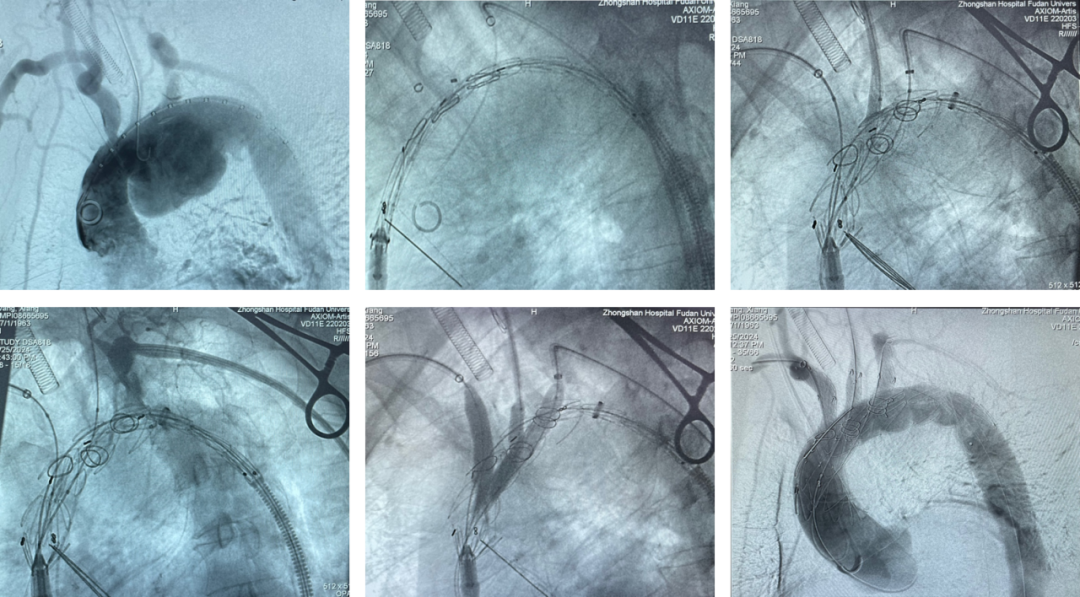

王X,男,57岁,主动脉弓动脉瘤。LSA、LCCA双内分支, IA开窗。

术中